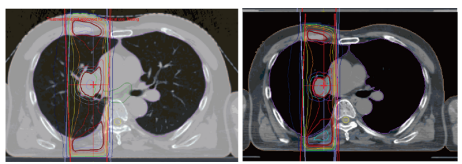

一位患有局部晚期NCSLC(cT3N1M0,IIIA期)的60岁男性同时接受了放化疗。患者接受了两个周期的顺铂(60mg/m2)加替加氟-吉美嘧啶-奥特拉西(120 mg/天)联合同步放射治疗(60 Gy/30 fr)。辐照设计如图1所示。照射区域靠近脊髓,可能与骨髓抑制有关。虽然3级中性粒细胞减少和血小板减少需要在第二个疗程中减少剂量,但患者还是完成了放化疗。然而,由于持续的血小板减少,使用德瓦鲁单抗的维持治疗被推迟。患者既往没有血液系统疾病。没有服用任何因果药物。

图1. 辐照设计。照射区域靠近脊髓